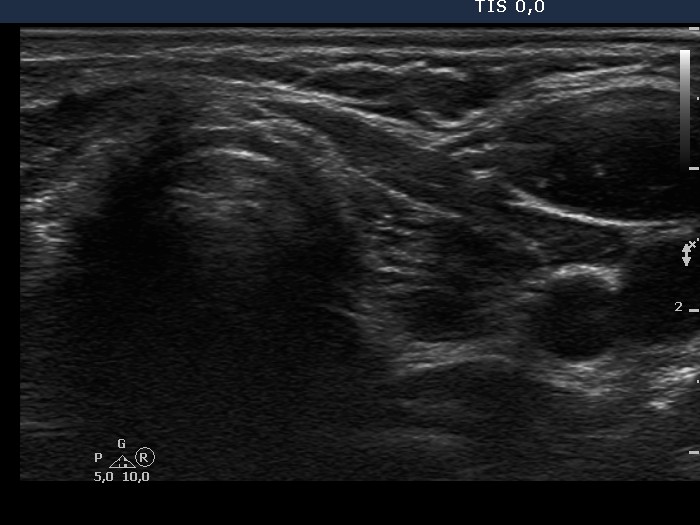

Chronic lymphocytic thyroiditis - Case 36. |

Clinical data: a 35-year-old woman with hypothyroidism replaced with 100 ug levo-tiroxin was referred for evaluation of thyroid nodules.

Ultrasonography: there were several circumscribed areas which in fact did not fit nodules. These are active foci of autoimmune thyroiditis.

Cytological report: benign Hashimoto's thyroiditis.